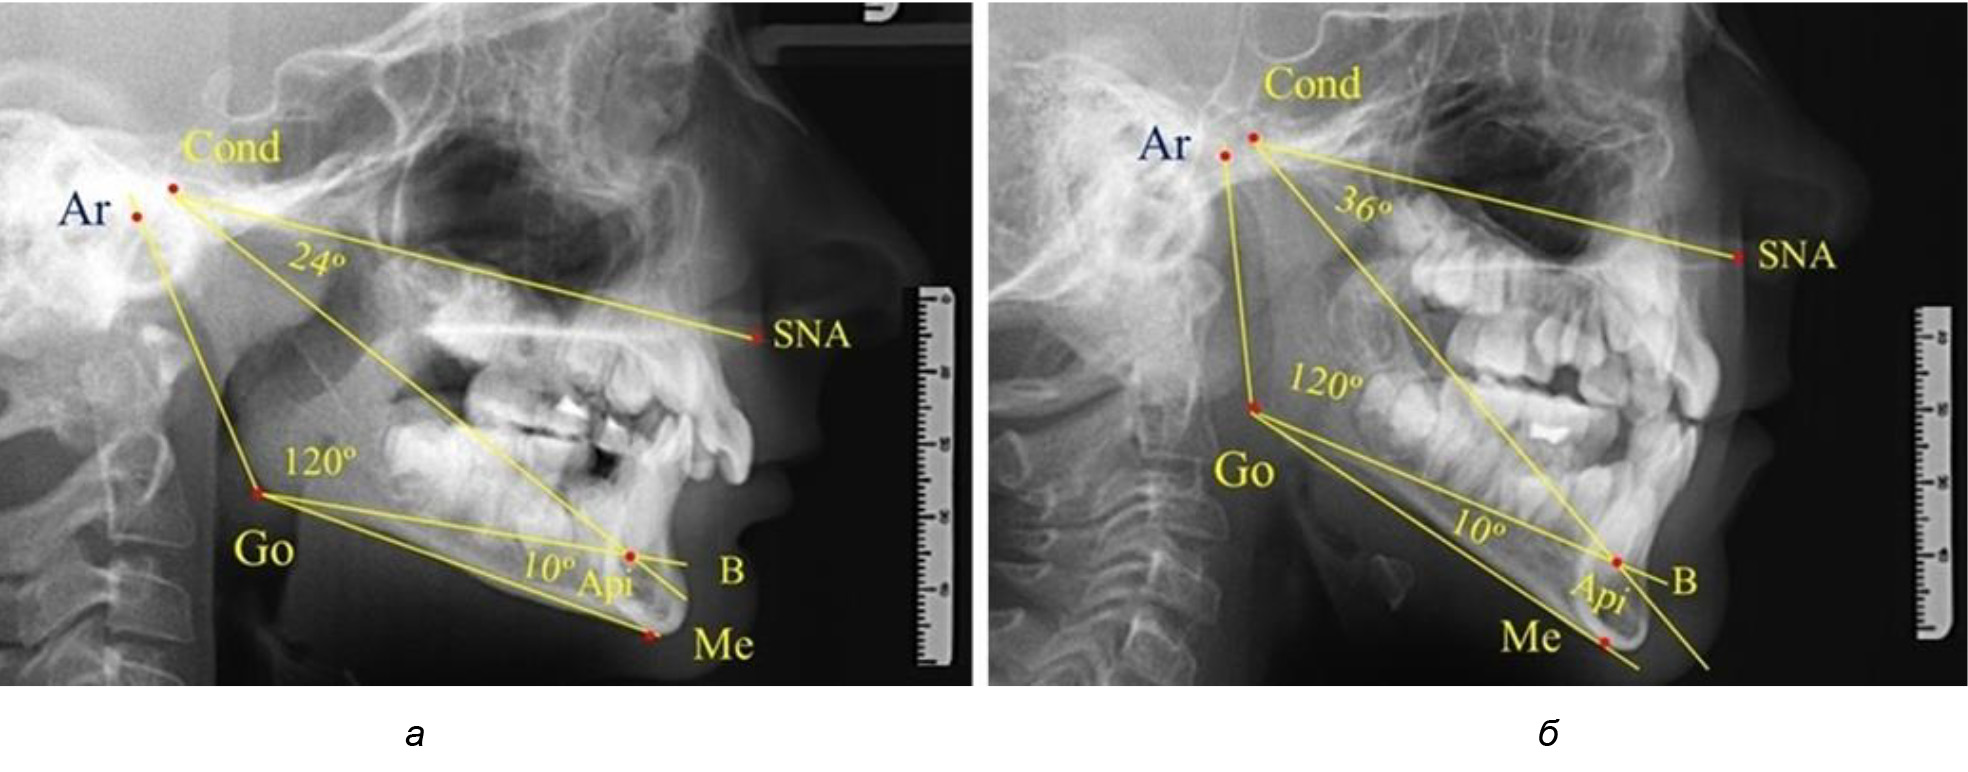

При анализе ТРГ 5 детей в периоде прикуса молочных зубов отмечено, что величина основного угла гнатической части лица SNA-Cond-Api, как правило, в норме составляла около 30°, и его величина была относительно стабильной у всех обследованных детей. В то же время угол нижней челюсти и его составляющие отличались вариабельностью параметров при различных показателях нижнечелюстного угла (рис. 4).

Рис. 4. Особенности ТРГ (а) и 3D-модели (б) в периоде прикуса молочных зубов

Таким образом, в периоде молочного прикуса с оптимальными окклюзионными соотношениями, несмотря на линейные размеры в вертикальном и сагиттальном направлении, которые, безусловно, меньше параметров взрослых людей, величина основного угла гнатической части лица SNA-Cond-Api соответствовала параметрам людей с полностью сформированным физиологическим прикусом постоянных зубов. Анализируя данные рентгенограмм детей в периоде сменного прикуса, отмечено, что величина основного угла гнатической части лица SNA-Cond-Api, так же как в молочном и постоянном прикусе, в норме составляла от 28 до 32°. В то же время угол нижней челюсти и его составляющие отличались вариабельностью параметров при различных показателях нижнечелюстного угла. Достоверных различий угла гнатической части после смены нижних медиальных резцов и прорезывания первых постоянных моляров (4 ребенка) не было; происходил очередной этап подъема высоты прикуса и увеличение линейных размеров костей гнатической части, однако угловые параметры были относительно стабильны. После смены всех резцов и замены первых молочных моляров первыми премолярами (6 человек) увеличивались линейные размеры при сохранившихся угловых показателях гнатической части лица (рис. 5).

Рис. 5. Варианты ТРГ после прорезывания ППМ и нижних резцов (а), всех резцов и первых премоляров (б)

Таким образом, в период сменного прикуса с оптимальными окклюзионными соотношениями, несмотря на увеличение линейных размеров в вертикальном и сагиттальном направлении, по сравнению с прикусом молочных зубов, величина основного угла гнатической части лица SNA-Cond-Api соответствовала показателям как постоянного, так и молочного прикуса с физиологическими окклюзионными соотношениями.

После смены всех молочных зубов (анализ 9 ТРГ) и после прорезывания вторых постоянных моляров (7 человек) происходил очередной этап подъема высоты прикуса с увеличением размеров костей гнатической части лица. Однако величина основного угла гнатической части лица SNA-Cond-Api, так же как в молочном и сменном прикусе, в норме составляла (30,02 ± 1,25)°, что не имело достоверных различий (р ˃ 0,05) с аналогичным параметром, анализируемом в других группах исследования. Угол нижней челюсти и его составляющие отличались вариабельностью параметров при различных показателях нижнечелюстного угла (рис. 6).